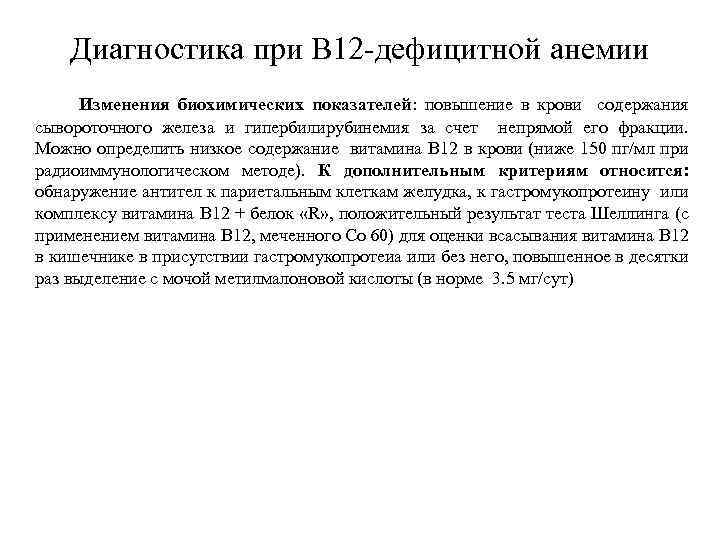

Диагностика при В 12 -дефицитной анемии Изменения биохимических показателей: повышение в крови содержания сывороточного железа и гипербилирубинемия за счет непрямой его фракции. Можно определить низкое содержание витамина В 12 в крови (ниже 150 пг/мл при радиоиммунологическом методе). К дополнительным критериям относится: обнаружение антител к париетальным клеткам желудка, к гастромукопротеину или комплексу витамина В 12 + белок «R» , положительный результат теста Шеллинга (с применением витамина В 12, меченного Со 60) для оценки всасывания витамина В 12 в кишечнике в присутствии гастромукопротеиа или без него, повышенное в десятки раз выделение с мочой метилмалоновой кислоты (в норме 3. 5 мг/сут)